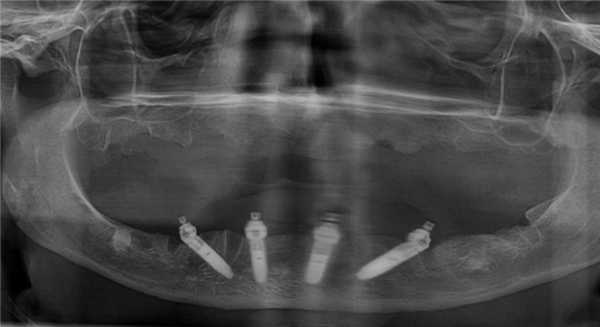

- Выполнение операции по концепции all-on-4 с использованием имплантатов Nobel Parallel CC по классическому протоколу Palo Malo (фото 4)

Справа был установлен один имплантат. Из-за большой протяженности зубного дефекта на левой стороне нижней челюсти установили три имплантата - оптимальное количество для поддержки мостовидного протеза из четырех металлокерамических коронок. На панорамном снимке видно расположение установленных имплантатов.